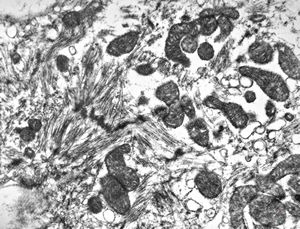

M, 7w. | mitochondrial cardiomyopathy … (N … nucleus, F … myofilaments,L … lipid droplets surrounded by megamito